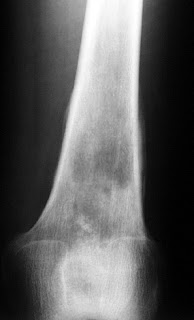

Radiographically, enchondromas appear as geographic, mildly expansile, lytic lesions, which may lead to mild cortical thinning. The zone of transition is narrow, although it can be lobular. A cartilaginous matrix (rings and arcs) is often present, less often in lesions occurring in the hands and feet. There is no cortical break through or host response in the absence of fracture. Enchondromas are usually monostotic, although multiple lesions can occur in the feet and hands. On MR, they have typical signal characteristics of chondroid lesions with low signal on T1 and very high signal on T2 (due to high water and mucopolysaccharide content).

Fig 1. Enchondroma in the distal femur. Note the lesion is geographic with response from surrounding bone. Cartilagenous matrix is present.